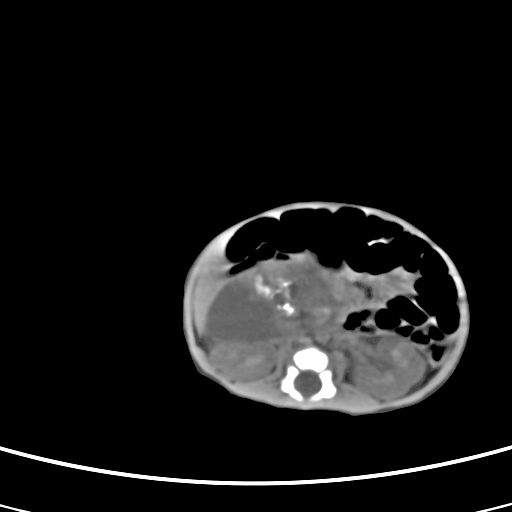

患儿,男性,出生后2天,在胎儿时b超已发现病变,患儿一般情况可。因病变部位偏向于右侧肾上腺区,目前考虑为神经母细胞瘤,不知各位能否支持。

反对定位在右肾上腺区的说法,那么神经母细胞瘤也可以暂时不予考虑。请看下图:

下面这幅图中,似乎可以见到肿瘤的薄包膜,其后与右肾之间的又是什么东西呢?这关系到肿瘤的定位、定性。我考虑病灶是位于肝十二指肠韧带内的畸胎瘤可能性比较大。请各位老师仔细看一下:

病灶巨大,位于右侧肾上腺区,与周围组织分界欠清,内见不规则钙化影,无明显脂肪组织,首先考虑神经母细胞瘤,但畸胎瘤不能排除。

定位后腹膜,定性:畸胎瘤与寄生胎相鉴别.请传骨窗.发现躯干骨或四肢骨就考虑寄生胎.